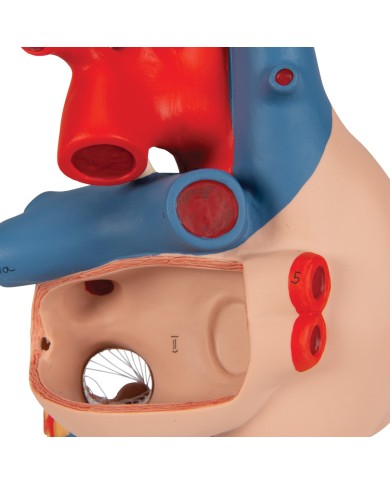

Modello di cuore di alta qualità scomponibile in 5 parti

Modello di cuore di alta qualità scomponibile in 5 parti

La parete anteriore del cuore è staccabile per poter vedere i ventricoli.

Realizzato in stampa 3D ad elevatissima risoluzione a colori.